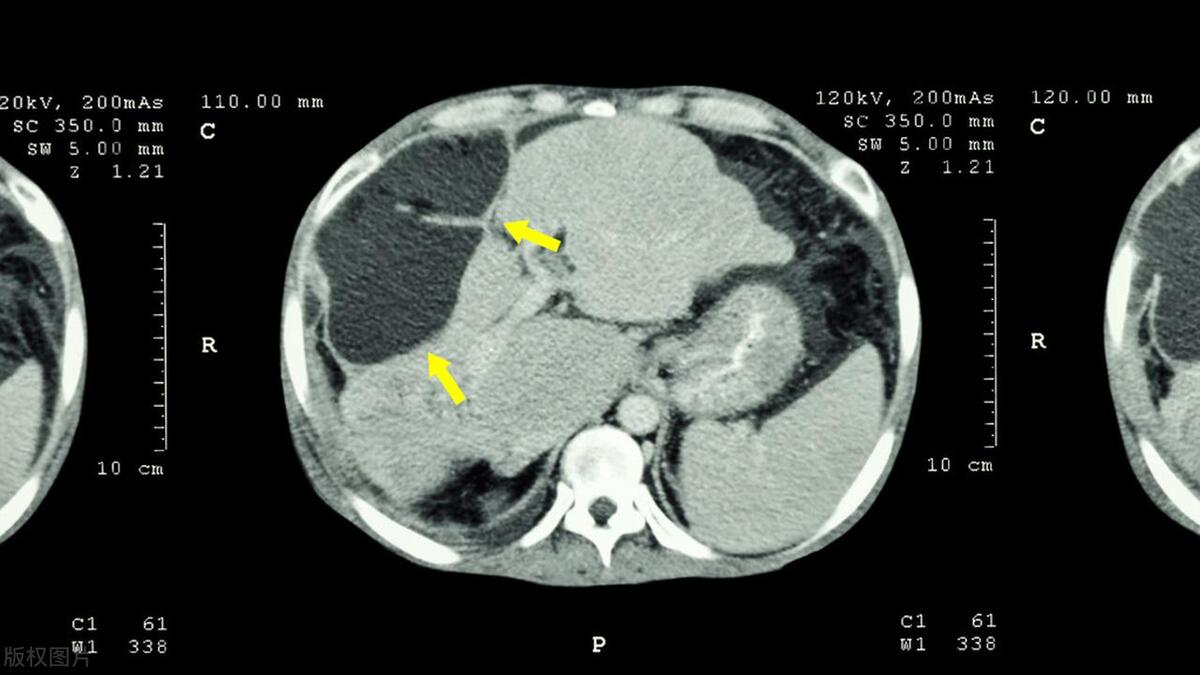

经过挂号、排队就诊、检查、复诊,过去了几个小时,然后当检查结果出来的那一刻,郑先生瘫坐在了地上:肝癌!

而且是晚期!